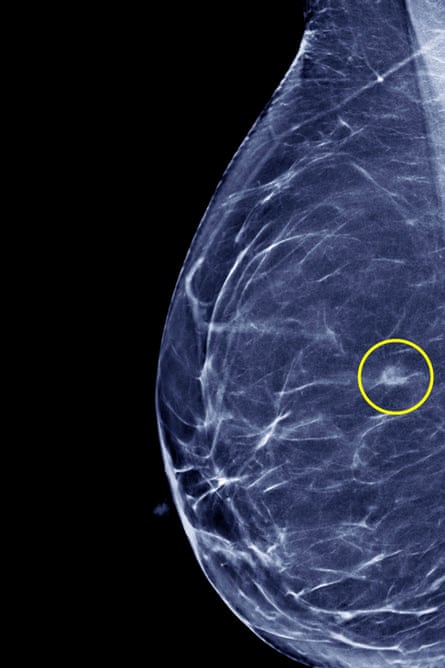

A cancerous tumour in the breast (circled), visible through a mammogram. Photograph: Science Photo Library

This was until two landmark studies, starting in the late 1990s and supported by Cancer Research UK, found that a smaller number of higher doses of radiotherapy were just as effective and minimised side effects, while reducing hospital visits for treatment from 25 to 15, spread over three weeks. In 2009, once the 10-year post-treatment outcome figures were in, the evidence changed the National Institute for Health and Care Excellence guidelines on radiotherapy for breast cancer. The efficacy of these developments along with others – more on which follows – is highlighted by the fact that the risk of breast cancer coming back within five years after treatment has dropped from around 10 in 100 people in the 1980s to between one and two in 100.